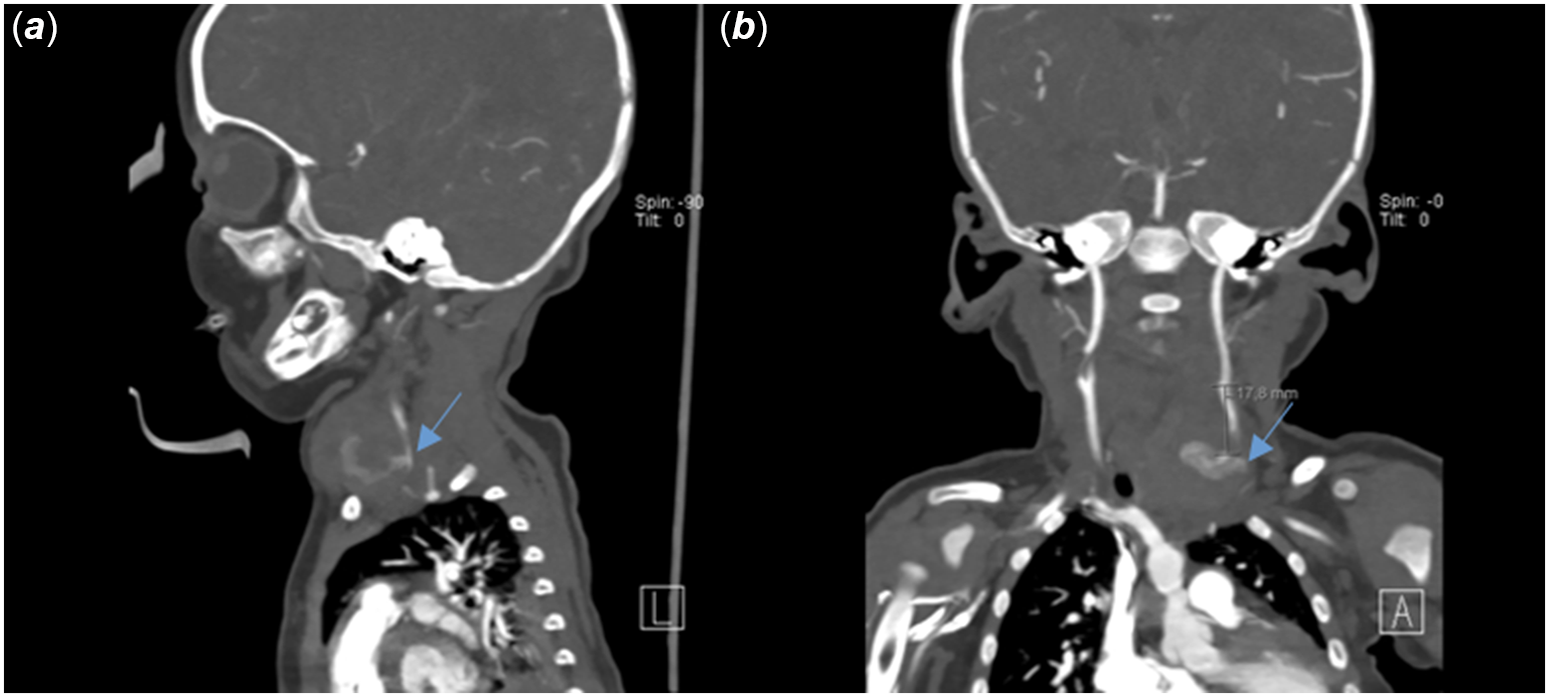

A 6-month-old girl was admitted to the hospital for evaluation for coarctation balloon angioplasty. In medical history, the patient was operated on due to aortopulmonary window, interrupted aortic arch, and aortic coarctation when she was 12 days old. Balloon angioplasty was performed for recoarctation 1 month later. Then, she underwent a second operation due to left phrenic nerve palsy. The patient was referred for evaluation due to recoarctation. On physical examination, she weighed 4.3 kg and revealed scars from previous surgeries around the left thoracotomy and left subcostal region. The femoral pulses were weak. A 2/6 systolic ejection murmur was heard in the interscapular region. On the echocardiogram, there were left ventricular hypertrophy and diastolic flow pattern in descending aorta. It was decided to perform a balloon coarctation angioplasty for the recurrence of the aortic coarctation. In the catheter laboratory, efforts to find access from femoral and axillary arteries were unsuccessful. Left common carotid artery access was performed by using an 18-gauge needle and 0.035-inch wire under ultrasound guidance, and a 4F sheath was inserted. Intravenous heparin 30 unit per kilogram was admitted. There were no complications during the procedure (Fig 1). The patient was discharged from the hospital one day after the procedure. After 10 days, the family noticed a prominent mass on the left side of the patient’s neck. The patient was called in for control. During the patient’s examination, a 2 × 2 cm pulsating mass on the left side of the neck, with no signs of infection on the skin, was noted (Fig 2). On ultrasound, a 2 × 2 cm pseudoaneurysm was detected adjacent to the left common carotid artery (Fig 3). To better assess the location. of the pseudoaneurysm, a CT angiography was performed. CT revealed a 3 × 3 cm pseudoaneurysm with a 3 mm connection with the left common carotid artery, located 2 cm below the bifurcation. Due to the pseudoaneurysm, the trachea and surrounding structures were noted to be shifted to the right side (Fig 4). The management was discussed with the department of interventional radiology. A stent graft was not suitable since the patient was an infant. Even the pseudoaneurysm neck was narrow, percutaneous thrombin injection still had a risk of distal emboli, and it was not possible to insert a filter into common carotid artery due to unattainable femoral access. With the department of cardiovascular surgery, it was decided upon to move forward with a surgical treatment plan. During the operation, considering the pseudoaneurysm sac’s growth direction, an incision was made lateral to the right sternocleidomastoid muscle. Sternocleidomastoid was excluded laterally, and the sac was partially exposed with a meticulous dissection. Proximal and distal parts of the carotid artery were identified and clamped after heparinisation. The pseudoaneurysm sac was excised, and the coagulum was removed. 1–2 mm needle hole on carotid artery was localised and closed with separated stitches (Fig 5). The clamps were removed, and the blood flow was re-established. The patient was extubated in the operating room and transferred to the paediatric ICU without any complications. The repeat ultrasound on the post-operative fourth day was normal, and the patient was discharged without any neurologic problems.

Figure 4. The sagittal section blue arrow shows the orifice of the pseudoaneurysm originating from the left common carotid artery (A). In the coronal section, it is observed that the pseudoaneurysm is approximately 2 cm below the bifurcation (B).